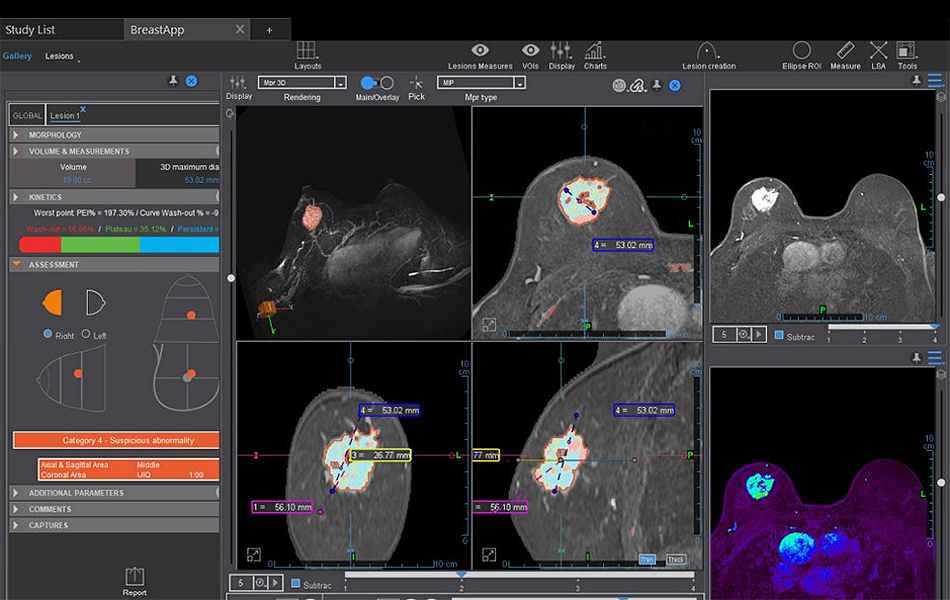

Olea Sphere® – MR Breast Advanced (breastscape®)

MR Breast Advanced (breastscape) is a semi-automated solution for diagnostic assistance in breast lesions. It provides automatic computation of the parametric maps, automatic segmentation of the lesion and calculation of the clinically relevant distances, lesion evolution follow-up, assistance to the structured preparation of the report, based on the latest edition of BI-RADS® Atlas, and creation of a report exportable as PDF.

Note: MR Breast Advanced (breastscape) is now available for sale in the U.S.